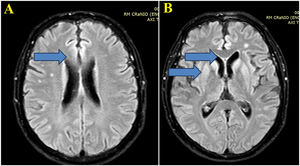

Case reportA 59-year-old man was diagnosed with HIV associated with Pulmonary Tuberculosis (TB) in late 2012 (at age 48) through ELISA and Western Blot serological tests, as well as a sputum culture for Acid-Fast Bacilli (AFB). He initially received treatment for TB, followed by Antiretroviral Therapy (ART) two weeks later, consisting of tenofovir (TDF), lamivudine (3TC), and efavirenz (EFV). Laboratory tests before starting ART showed a CD4 count of 18 cells/mcL (4 %) and a CD8 count of 203 cells/mcL (45 %), with a Viral Load (VL) of 224,906 copies/mL (Log=5.35). After completing TB treatment, his CD4 count increased to 167 cells/mcL (17.9 %), and his VL decreased to 82 copies/mL (Log=1.91). The patient developed Immune Reconstitution Inflammatory Syndrome (IRIS) with cervical lymphadenitis, which was managed with aspiration, and experienced persistent peripheral neuropathy during TB treatment, requiring pyridoxine supplementation. During this period, he also developed systemic arterial hypertension, type 2 diabetes mellitus, dyslipidemia, and keratitis related to past pterygium surgery. After 11-years of regular antiretroviral therapy, which was later switched to lamivudine and dolutegravir, he maintained persistent undetectable HIV viremia and adequate pharmacological control of systemic arterial hypertension, type 2 diabetes and hypercholesterolemia, using losartan 50 mg/day, metformin 1g/day, and atorvastatin 10 mg/day. He persistently reported bilateral 'boot distribution' paresthesia, attributed to an adverse reaction to isoniazid. During a routine follow-up on May 8, 2023, he mentioned that his partner had been complaining about him forgetting personal items, such as his wallet and car keys, despite the patient’s own disagreement. At this time the International HIV Dementia Scale scored seven points, and a brain MRI was recommended. Unfortunately, he did not undergo the requested brain MRI and returned only three months later, experiencing a sudden worsening of symptoms, including increased neuropathy, weight loss, social withdrawal, and somnolence. Neurological examination revealed temporal disorientation, ataxia, a left Babinski sign, hyperreflexia in the right patellar tendon, exhausted clonus in the right foot, and dysdiadochokinesia. Myoclonus was not present. Hospitalization was recommended, when evaluated by a neurologist, and MRI (in August 9) showed a restricted diffusion hypersignal located bilaterally in the insula, basal ganglia, and anterior cingulate cortex (Fig. 1). Seventeen days after this first and brief hospitalization, MRI showed symmetric and bilateral hypersignal in the caudate and putamen, as well as in the superior frontal gyri (Fig. 2). Concurrent laboratory tests showed no abnormalities, including a non-reactive VDRL and normal renal, thyroid, and liver function. A lumbar puncture was also performed, and partial analysis of the Cerebrospinal Fluid (CSF) revealed normal cell counts and glucose and protein levels. Tests for pyogenic bacteria, fungi, and tuberculosis and PCR for herpes simplex virus types 1 and 2 were all negative. RNA PCR for HIV in the CSF was also negative. In addition, CSF autoantibodies for autoimmune and paraneoplastic encephalitis and 14-3-3 protein analyses were requested. At this point, we suspected rapidly progressive dementia, with prion disease and immune-mediated encephalitis considered as the main possibilities. Due to the delay in obtaining the 14-3-3 protein results, the patient was hospitalized for pulse therapy with methylprednisolone (1.0 g/day for 5-days), followed by intravenous immunoglobulin (IVIG – 2.0 g/kg for 5-days). During the second hospitalization (lasted 56-days), repeat MRI showed the same abnormalities described above, but the patient’s condition worsened, with further memory decline, spastic tetraparesis, hypophonia, and bradykinesia in both the upper and lower limbs. Furthermore EEG video was performed due to its longer duration in an attempt to capture changes characteristic of CJD, such as triphasic waves. The disease progression was rapid, leading to a state of akinetic mutism. A Gastrostomy Tube (GTT) was placed due to dysphagia. The patient developed a fever caused by aspiration pneumonia, which was treated with antibiotics, and was discharged with the GTT, spastic tetraparesis and akinetic mutism. After 60-days, the 14-3-3 protein results were received, revealing high titers, and the family was consulted about initiating palliative care to avoid invasive measures. During his course, the patient underwent 3 EEGs, all of which revealed only nonspecific slowing. RT-QuIC analysis of the CSF was positive. He passed away 6-months after the onset of neurological symptoms.

(A) Brain MRI images with Axial FLAIR sequence at the centrum semiovale show a small cortical hypersignal in the superior frontal gyrus bilaterally (blue arrow). (B) Brain MRI images at the basal ganglia level also demonstrate a symmetric and bilateral hypersignal in the caudate and putamen, as well as in the superior frontal gyri (blue arrow).